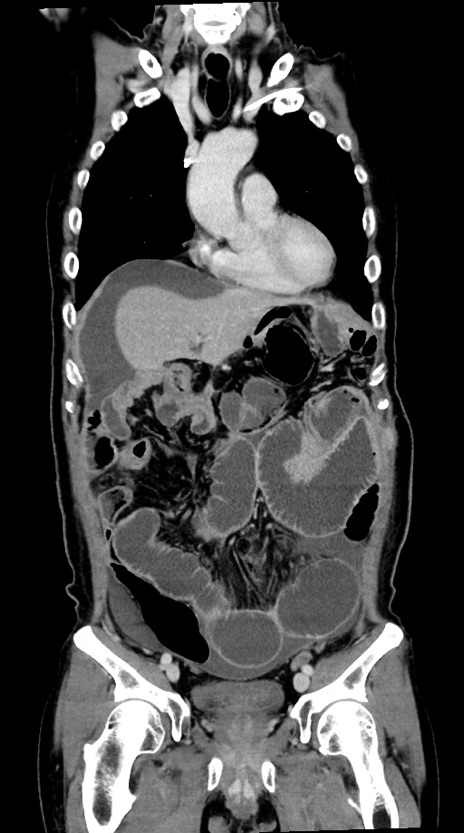

症例28(冠状断像)

【症例】60歳代男性

【主訴】嘔吐

【現病歴】胃癌にて胃全摘後。食思不振が悪化し、夜中に嘔吐することがある。

【既往歴】胃癌、胃全摘、脾摘、胆摘後

【データ】WBC 5900、CRP 10.56